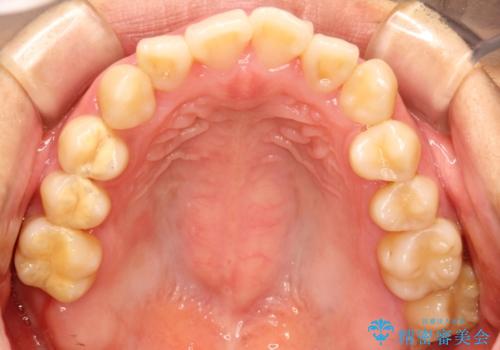

上下の歯のガタガタ ワイヤーでの抜歯矯正で整った歯並びへ

- 上下の歯のガタガタを治したいとのことで来院されました。

がたつきの度合いが強いのと、口元をなるべく引っ込めたい希望がありましたので、ワイヤーでの抜歯矯正となりました。